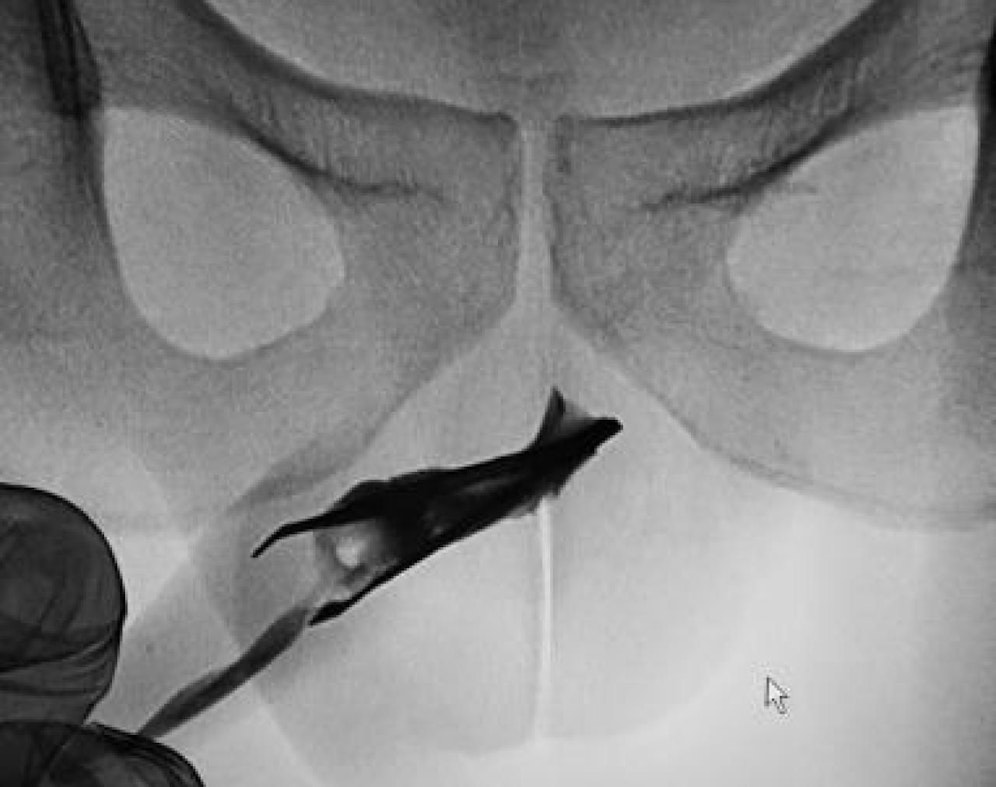

Man möchte sich nicht vorstellen, wie es sich anfühlen muss, wenn man eine 8 Zentimeter lange Pinzette in die eigene Harnröhre einzuführen versucht. Doch genau das hat ein damals 18-jähriger Mann vor vier Jahren probiert – und auch geschafft. Das beweisen die Röntgenaufnahmen, die seine Ärzte nun in den "Urology Case Reports" präsentieren.

Nachdem Untersuchungen die Aussagen des Patienten bestätigt hatten, konzentrierten sich die Ärzte darauf, den Fremdkörper zu entfernen. Eine nicht ganz einfache Angelegenheit. Denn die Pinzette steckte geöffnet in der Harnröhre. Bei jedem Versuch, den Greifer zu entfernen, stießen die Enden ins Fleisch.

Um dem entgegenzuwirken, mussten gleich mehrere Chirurgen ans Werk. Während der eine den Fremdkörper vorsichtig herauszog, hantierte ein weiterer am Penisschaft und drückte von außen die sich im Innern befindende Pinzette zusammen – mit Erfolg.